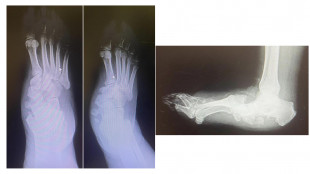

Arriva in Italia il laser con IA per rimuovere la cataratta

All'Irccs di Negrar. Mappatura robotica dell'occhio consente intervento personalizzato